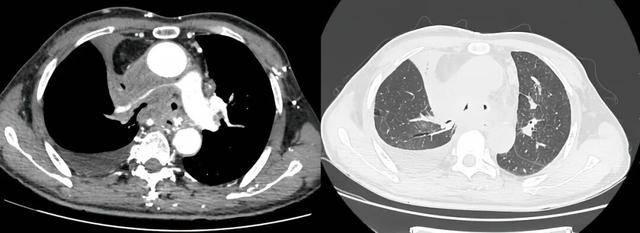

术前受压变窄的右肺动脉和中央气道

手术过程

同期置入支架后狭窄明显改善